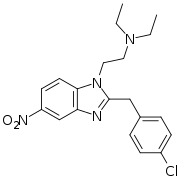

Benzimidazoles

Structures

| Benzimidazoles | ||||

|---|---|---|---|---|

|

|

|

|

|